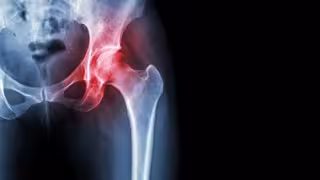

Necrosis avascular de cadera

Necrosis avascular de cadera - HOSPITAL LA LUZ - Archivo